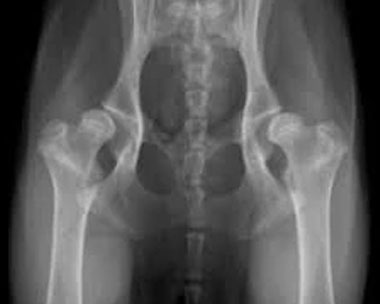

股関節と肘関節のX線検査とは - BVAシステム

BVAとは「British Veterinary Association(英国獣医師会)」の略で、この検査方式はイギリスで開発されたものです。スコアリングは左右両方の股関節に対して行われ、10項目に分けて評価し、それぞれの点数を合計して最終スコアを算出します。どれか1つの項目で4以上のスコアを示す場合、その犬は早期段階で退行性変化の兆候があるとされ、繁殖には不適と判断されます。犬種によってはスコアが高く出ることがあり、その場合は繁殖には向きません。合計スコアが100を超える場合もあります。

私たちの犬たちは長年にわたり、常に非常に低いスコアを維持しています。基本的には、オーストラリア国内のラブラドゥードルの平均値(合計12.75)を下回る犬を使用しています。オス犬に関しては、さらにスコアが低いことを絶対条件としており、基準を緩めるつもりはありません。

PennHIPとは

PennHIPは、股関節の状態を詳しく調べるための新しい検査方法で、将来、関節炎や股関節形成不全といった問題が起こる可能性をより正確に予測できるのが特徴です。PennHIPでは、股関節の角度やゆるみ具合、そして関節に変化がないかなどを電子的に測定します。結果はパーセンタイルという形で示され、ラブラドゥードルの場合は「犬種の平均範囲内」に収まっていることが理想とされています。

Kiwi Prideでは、検査の結果は獣医師と一緒に確認し、次の世代の子犬たちがより健康で安定した関節を持てるよう、最適な組み合わせを考えて繁殖を行っています。

PennHIPは、これまでのBVA方式よりも新しく、より正確に健康状態を把握できる検査です。WALA加盟犬舎のKiwi Prideでは、撮影したレントゲン画像はアメリカに送られ、専門機関で正式にスコアがつけられデータベースに記録、透明性を持って公開されます。